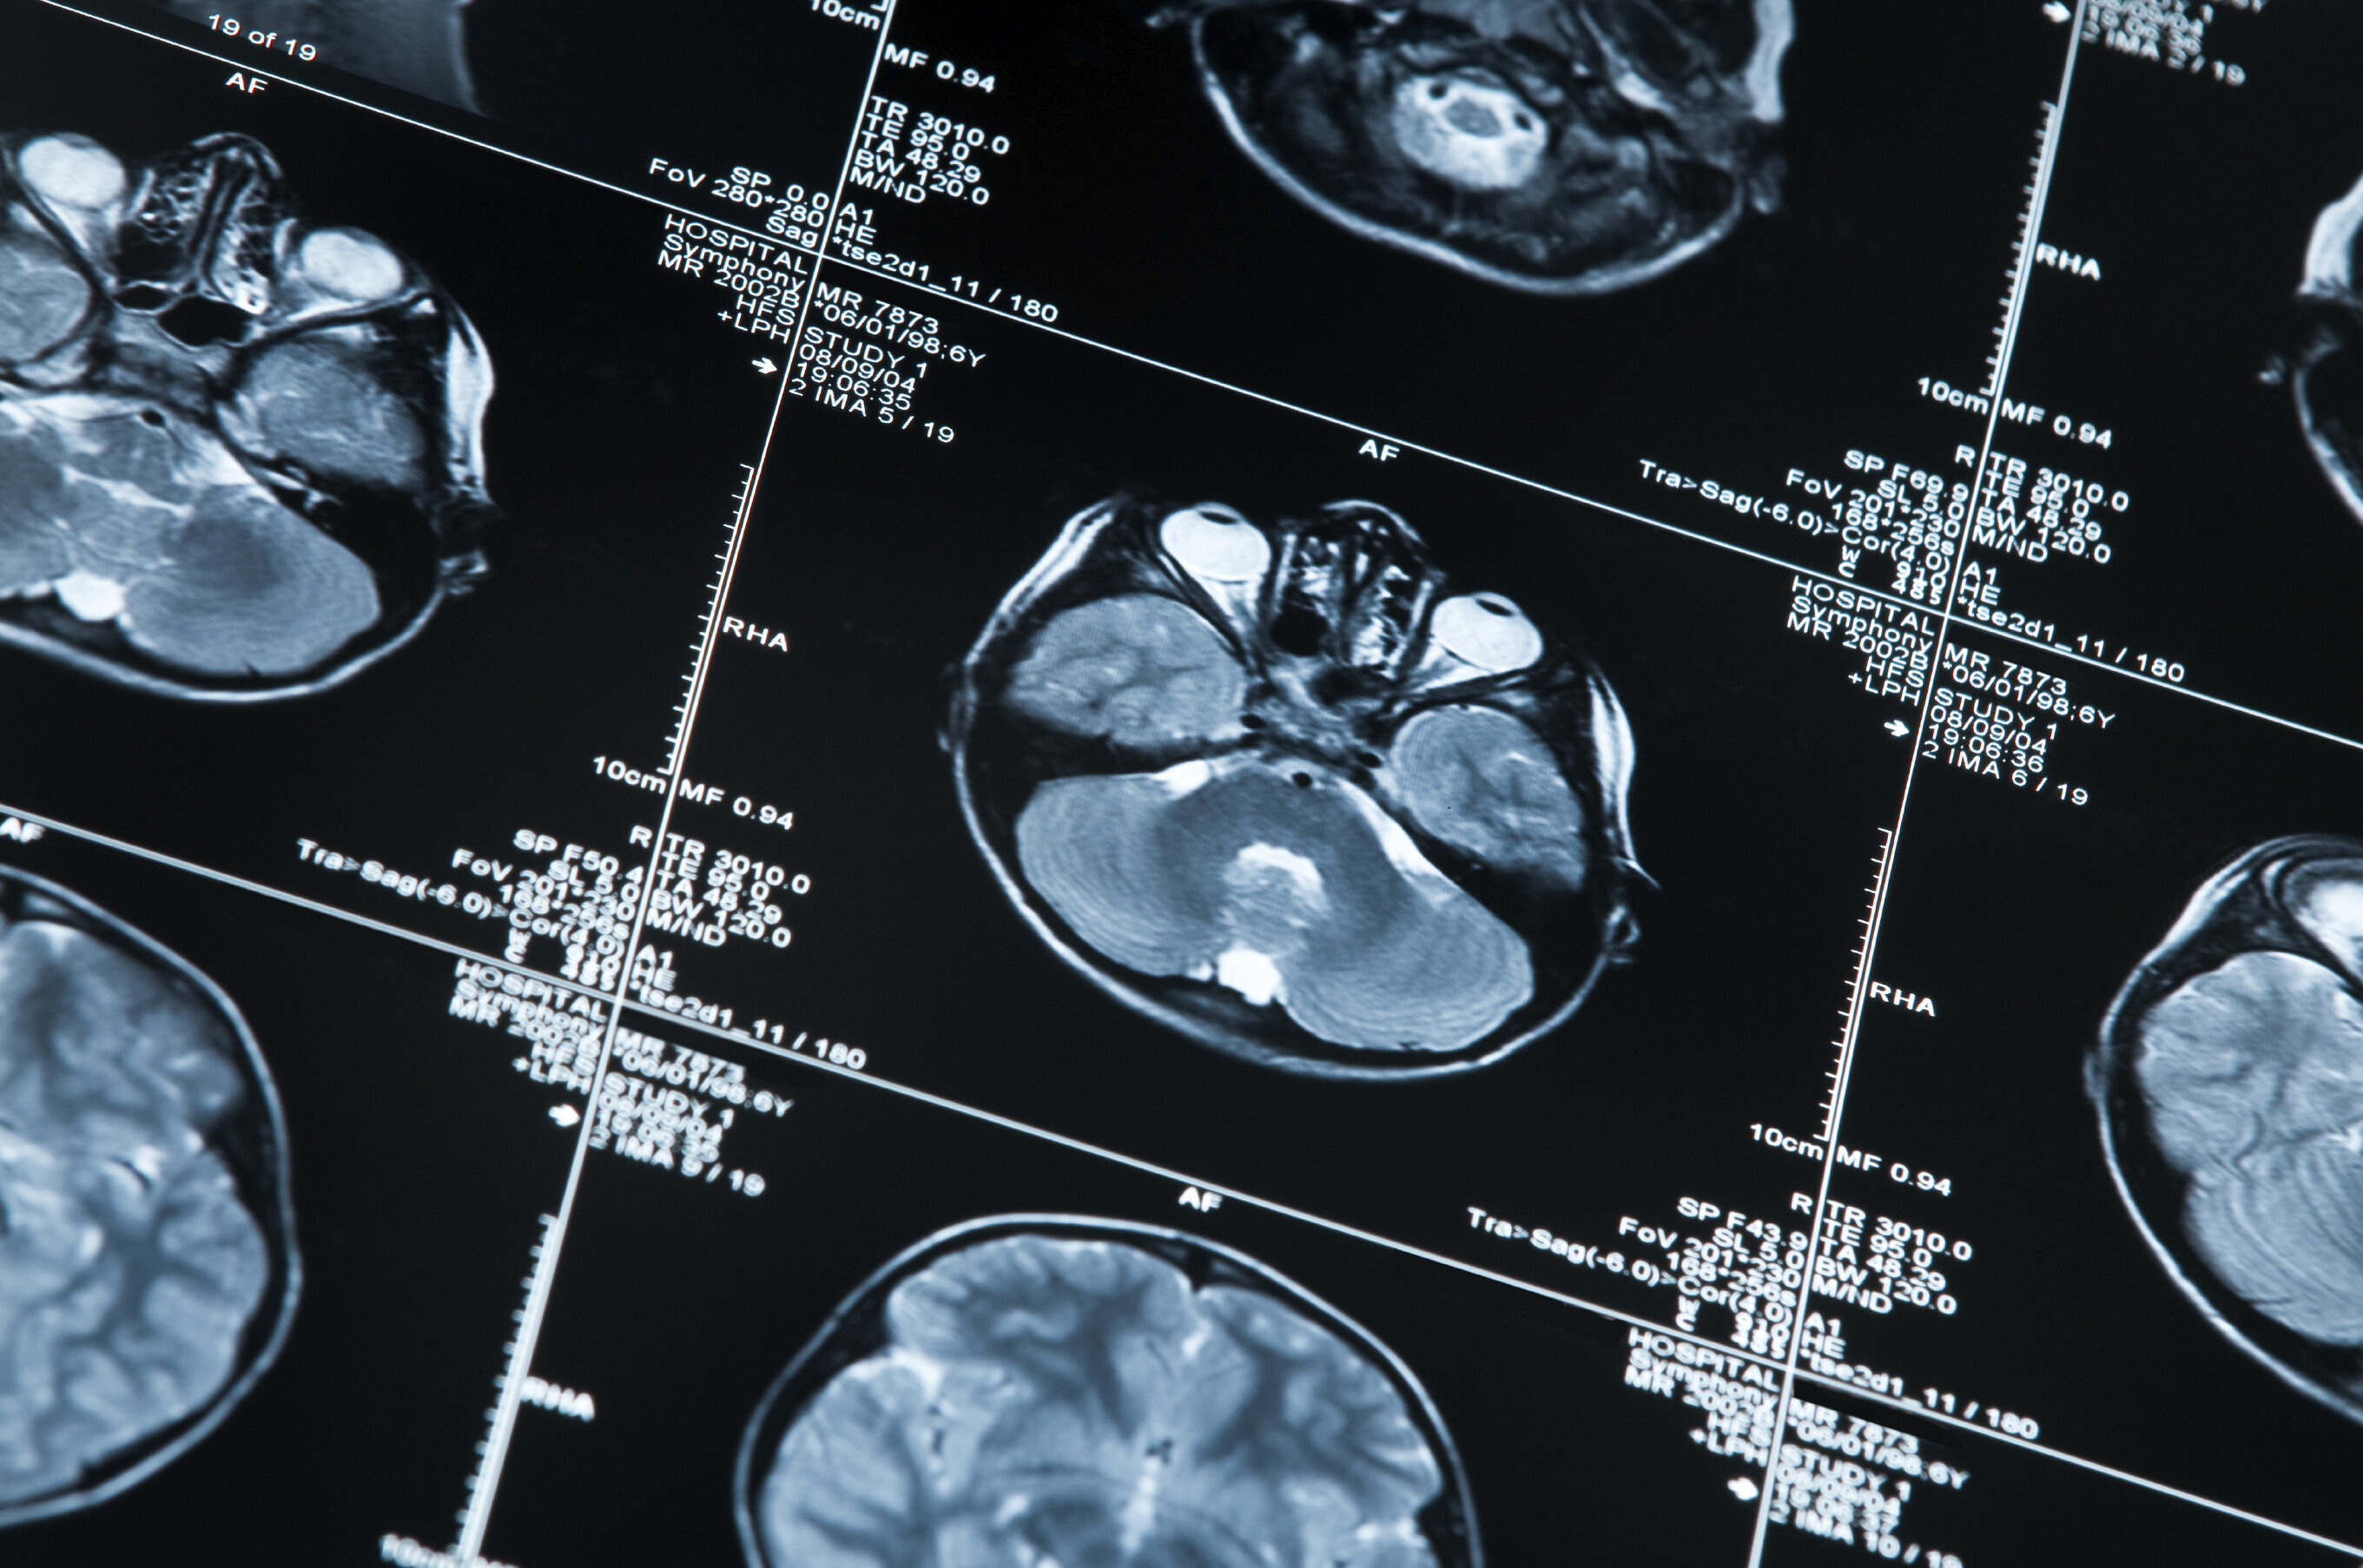

MRI scan of a human head

Recently completed EMPIR project Innovative measurements for improved diagnosis and management of neurodegenerative diseases (15HLT04, NeuroMET) developed reference measurement procedures to accelerate the uptake of minimal invasive methods for the early diagnosis and monitoring of the progression of neurodegenerative diseases such as Alzheimer’s and Parkinson’s. The research explored innovative techniques for early diagnosis and monitoring, based on non-invasive blood and saliva tests, in-vivo magnetic resonance approaches and cognitive assessments.